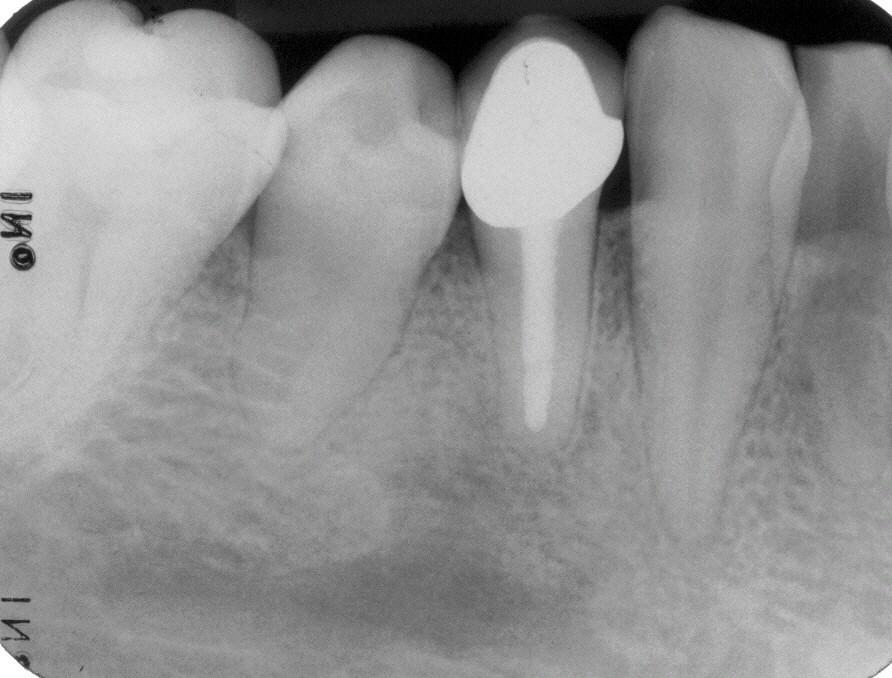

Wurzelfüllung

Wurzelfüllung im Januar 1997 in lateraler Kondensation mit normierter Guttapercha und AH 26. In der gleichen Sitzung wurde ein Titanstift adhäsiv inseriert mit dessen Hilfe der adhäsive Aufbau des Zahnes erfolgte